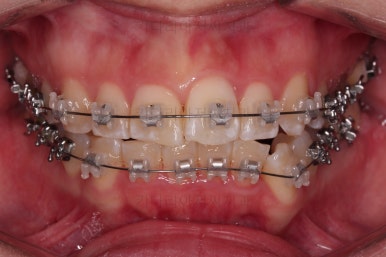

초진 시 입안의 모습입니다.

전반적으로 치열이 삐뚤고, 특정 앞니는 톡 튀어나가 미적으로 좋지 못한 상황이었습니다.

이갈이, 이악물기 습관도 있어서 앞니는 삐뚤어진 채로 치아가 많이 갈려있는 상황이었습니다.